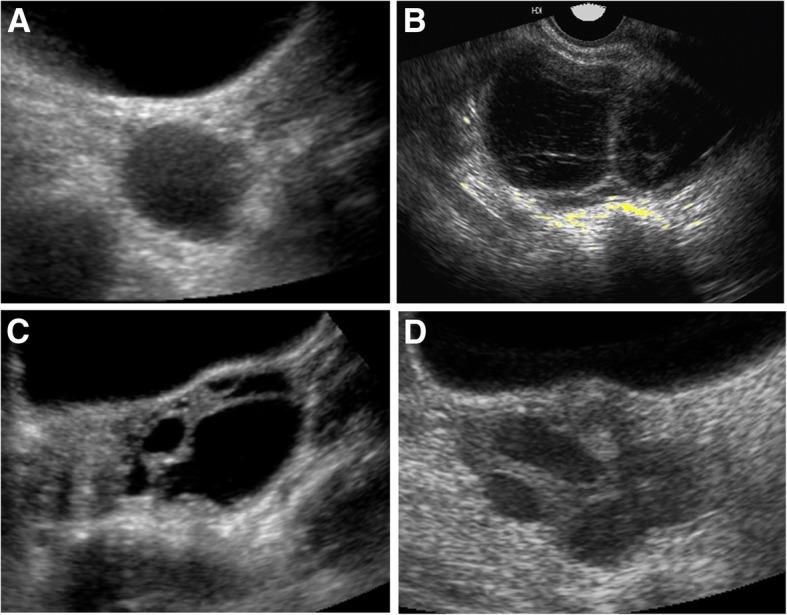

Autonomous ovarian activation with recurrent estrogen-producing cysts is a hallmark feature of the rare bone and endocrine disorder fibrous dysplasia/McCune-Albright syndrome. Precocious puberty in girls with McCune-Albright syndrome has been well-described, however long-term effects on gynecologic and reproductive function are unknown. Concerningly, case reports have described poor skeletal outcomes associated with pregnancy in women with fibrous dysplasia.

具有复发性产生雌激素的囊肿的自主卵巢激活是罕见的骨骼和内分泌疾病纤维发育不良/ McCune-Albright 综合征的显著特征。 McCune-Albright 综合征女孩的性早熟已有很好的描述,但是对妇科和生殖功能的长期影响尚不清楚。令人担忧的是,病例报告描述了与患有纤维发育不良的妇女的妊娠相关的不良骨骼结局。